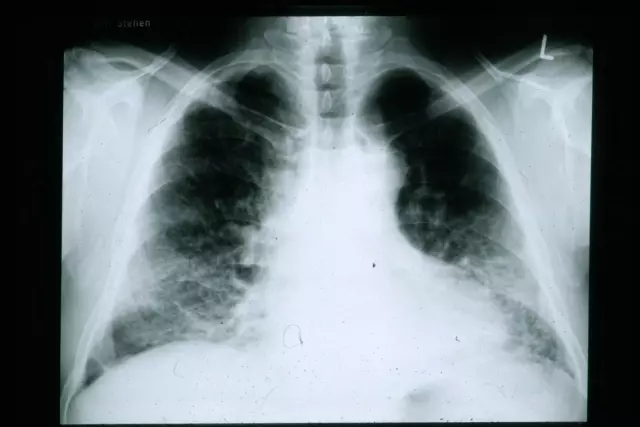

Kao svoju primarnu djelatnost ističe kompletne usluge na području respiratorne dijagnostike.

Bavi se specijalističko - konzilijarnom pulmološkom djelatnošću u kojoj slijedi isključivo najviše standarde.

Kroz 15 godina uspjeli smo, zahvaljujući Gradskom uredu za zdravstvo, opremiti ustanovu najkvalitetnijom radiološkom i pulmološkom aparaturom.